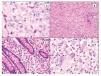

La imagen histológica del SH puede ser variable, pero por lo general están compuestos de células grandes (> de 20 μm) usualmente de redondas a ovales, con pleomorfismo acentuado (Figura 4). Se han descrito células de aspecto epitelioide y fusiforme con formación focal de empalizadas, lo que puede simular tumores de vaina nerviosa periférica.43

Figura 4. Histopatología del SH. A) Células grandes con abundante citoplasma eosinófilo (epitelioides) con pleomorfismo moderado. B) Aspecto fusiforme del sarcoma histioítico. C) Colon infiltrado por SH con células pleomórficas de aspecto epitelioide. D) Células de SH con pleomorfismo acentuado asociado a abundante infiltrado inflamatorio de neutrófilos.

El citoplasma es abundante y eosinófilo y pueden tener vacuolas finas. Es usual encontrar células bi o multinucleadas (Figuras 5A y 5B) y ocasionalmente hemofagocitosis por las células neoplásicas (Figuras 5C y 5D). Los núcleos generalmente son redondos a ovales o irregularmente lobulados, y a menudo son excéntricos con cromatina usualmente vesicular. Las figuras mitóticas varían de uno a 64 por 10 campos de x40,7 con áreas variables de necrosis y angio-invasión. Un dato que es muy característico de estas neoplasias, es la presencia de células reactivas asociadas como linfocitos, células plasmáticas, histiocitos y eosinófilos en variable cantidad, que en ocasiones pueden ser tan abundantes que las células neoplásicas aparecen ocultas por el intenso infiltrado inflamatorio, lo simula un proceso reactivo. Esta última característica es particularmente común en el SH que involucra sistema nervioso central.39 Cuando el SH afecta ganglios linfáticos, generalmente pierde su arquitectura por la proliferación de células neoplásicas citológicamente malignas que semejan histiocitos (Figura 5D).